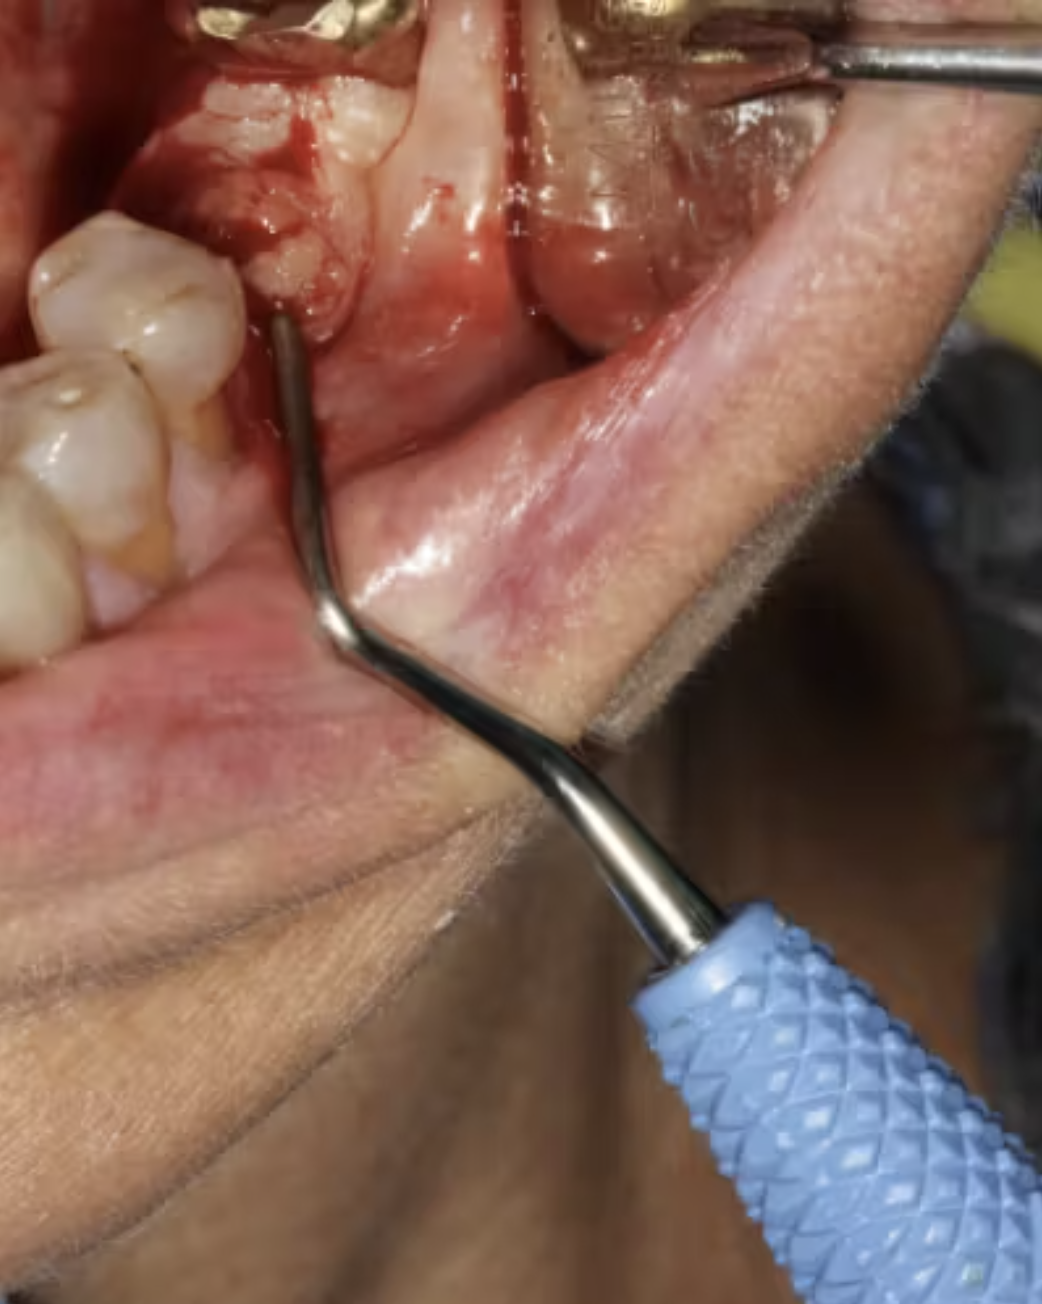

Ngoài ra, chiếu laser khử khuẩn mô mềm quanh vùng implant thất bại giúp giảm viêm và cải thiện quá trình lành thương.

(Hình 4: Khử trùng mô mềm bằng laser trong quá trình tháo implant để hỗ trợ lành thương)